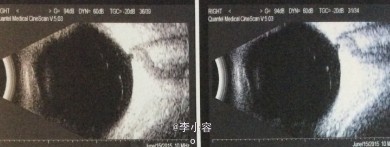

眼部检查: 视力:VOD:0.6 ,VOS:0.7,IOP:OD 45.4mmHg,OS 12.0mmHg,右眼结膜无充血,角膜透明,中央前房深度2CT,周边裂隙状,虹膜未见萎缩,瞳孔5×5mm,晶体混浊,眼底C/D=0.95,左眼结膜无充血,角膜清,中央前房深度2CT、周边裂隙状,瞳孔大小正常,晶体混浊,眼底C/D=0.5。 房角:右眼:N4(全粘闭) 左眼:N4(粘闭<1/2)

双眼原发性慢性闭角型青光眼(晚期 OD 早期 OS) .双眼老年性白内障 、 处理:右眼小梁切除术+前房成形术+虹膜周边切除术 左眼虹膜周边切除术

右眼视力0.5,眼压12mmHg滤过泡弥散隆起,2根可调缝线在位,角膜透明,ACD=3.5CT,PACD=1/4CT,房水细胞(+),虹膜周切口通畅,瞳孔约5×5mm,晶体混浊,眼底网膜平伏,C/D=0.95。 左眼结膜切口对合好,角膜透明,ACD=3.5CT,PACD=1/4CT,房水细胞(+),虹膜周切口畅,瞳孔3×3mm,对光反射存在,晶体混浊,眼底网膜平伏,C/D=0.5。 讨论:晶体因素导致的瞳孔阻滞是原发性慢性闭角型青光眼发病的主要诱因,包括晶体较厚,前、后表面曲率较大和相对位置偏前、虹膜晶体接触距离较大等. 病人常常具有眼轴短、前房浅的特点,容易发生房角粘连.视野缺损的程度与房角粘连程度成正相关,房角粘连范围愈广,视野缺损倾向愈大.眼压也与房角粘连程度成正相关,粘连的范围愈大,眼压值趋向愈高.提示房角粘连是慢闭发展的重要因素.虹膜周边激光切开术和小梁切除联合虹膜根部切除术都可以改善前房深度,但房角粘连范围大于180 °时,小梁切除术效果更明确,虹膜周边激光切开相对无效.